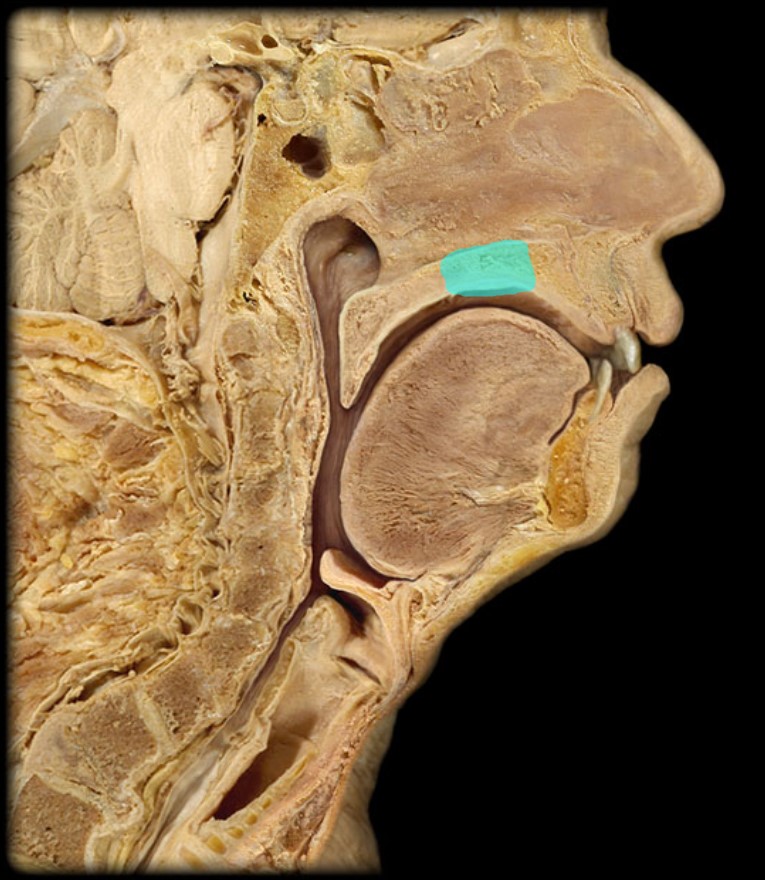

Anatomy 5 - Bifurcated Skull

29 Terms

Uvula

17

New cards

Soft Palate

18

New cards

Palatine Bone

19

New cards

Maxilla

20

New cards

Pharyngeal Tonsil

21

New cards

Auditory Hiatus

22

New cards

Torus Tubarius

23

New cards

Sphenoid Sinus

24

New cards

Inferior Nasal Concha

25

New cards

Middle Nasal Concha

26

New cards

Superior Nasal Concha

27

New cards

Nasal Vestibule

28

New cards

External Nares

29

New cards

Frontal Sinus